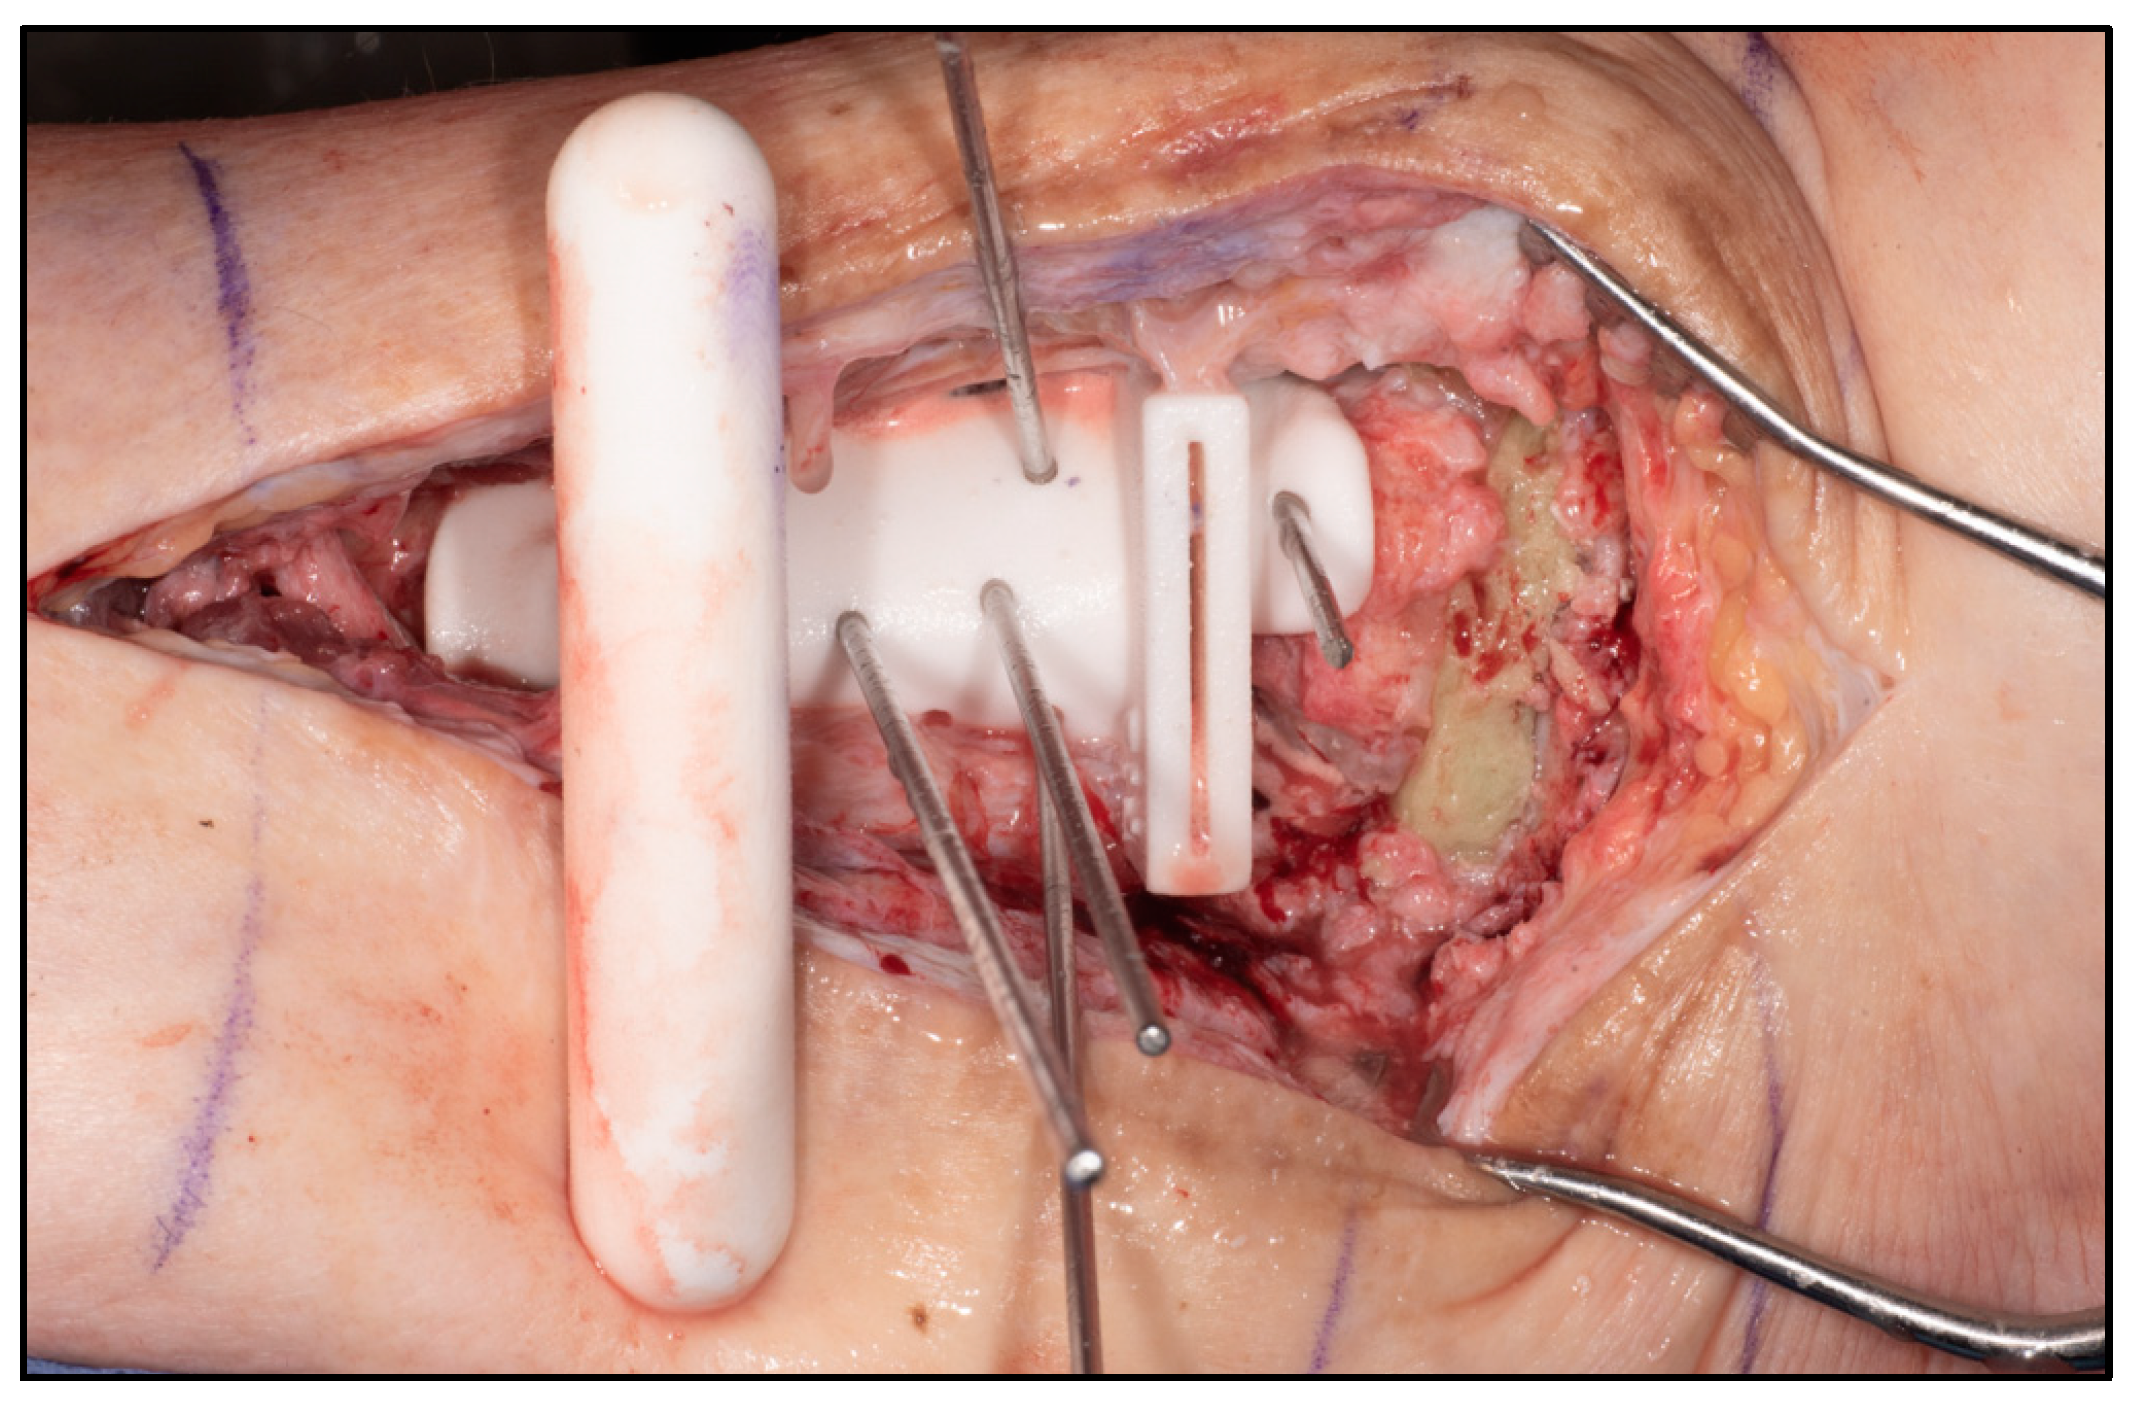

2.2. Surgical Technique